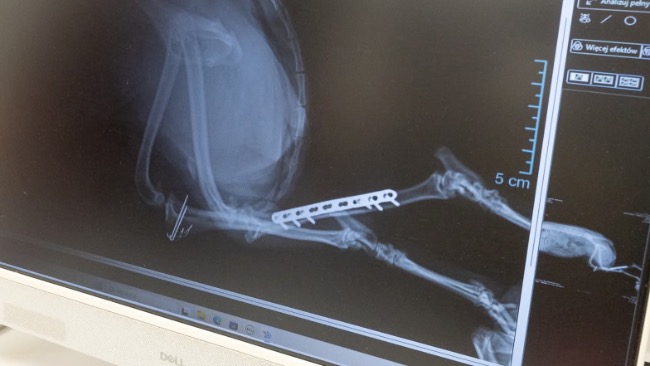

Oczy wymagają pilnej konsultacji okulistycznej. Serduszko musi zostać zbadane przez kardiologa. Zdjęcia RTG odsłoniły przerażającą prawdę o stanie Jej nóg. Obie były kiedyś połamane. Płyty w kościach sugerują, że ktoś próbował Ją poskładać, ale na tym się skończyło.

Laura nadal kuleje. Nadal cierpi. Każdy krok sprawia Jej ból. Przed Nią bardzo długa i trudna droga. Operacja ortopedyczna, a potem rehabilitacja są jedyną szansą, aby mogła żyć bez bólu i strachu.